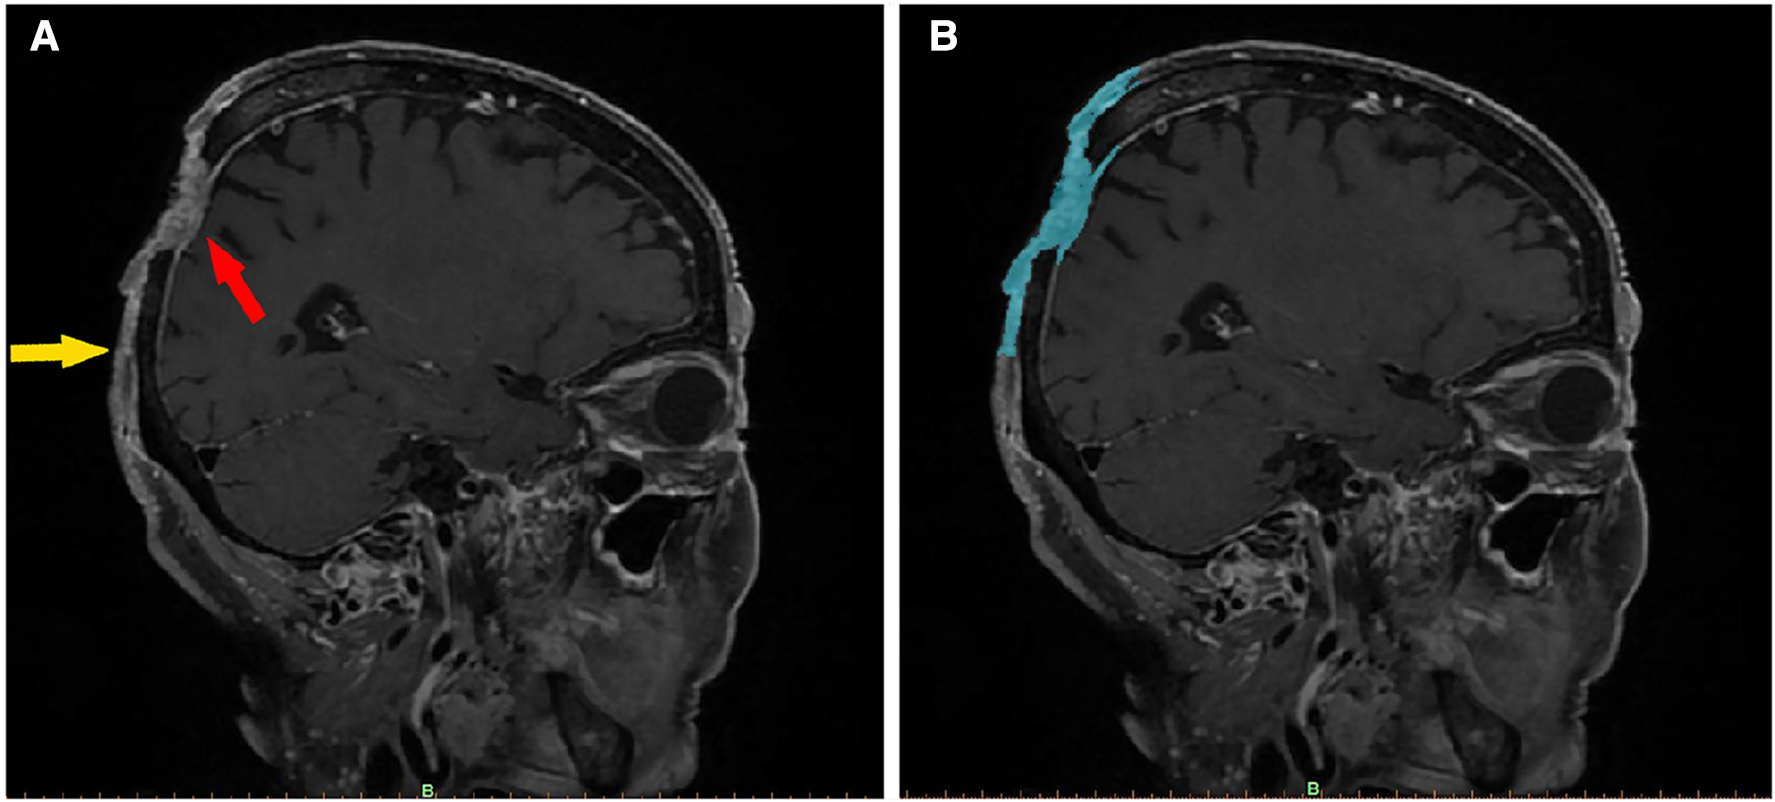

Figure 1

Imaging features of a scalp SCC (enhanced fat-saturated T1WI 3D CUBE sequence). In image (A), the red arrow indicates the main part of the tumor, which has an irregular, mixed signal, has invaded the dura mater, and is pressing inward. The yellow arrow marks the boundary of the tumor, the upper part of which is connected to the main part of the tumor. The skin is adhered to the periosteum, and the subcutaneous signal disappears. Image (B) shows the same section, segmented using Mimics software. The blue area denotes the imaging range. After being segmented layer by layer, the images were merged to create a 3D tumor model.